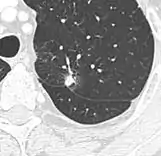

Round well-delineated solid lung nodule with smooth border.[9]